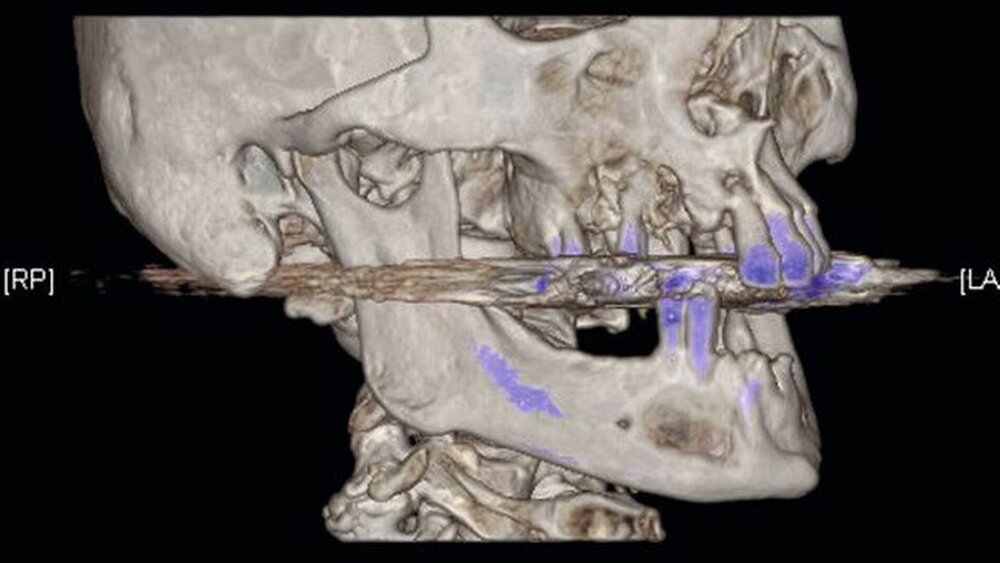

Die Computertomografie der Nasennebenhöhlen (NNH-CT) (nativ) zeigte dann das Ausmaß der knöchernen Destruktion. Neben der ausgedehnten generalisierten Nekrose des Oberkiefers konnte nebenbefundlich eine zystische Läsion im Bereich des Unterkiefers Regio 41 bis 45 diagnostiziert werden. Voraussichtlich ging diese vom Wurzelrest des Zahnes 41 aus. Weiterhin bestand eine totale Verschattung beider Sinus maxillaris und eine akzentuierte Lymphadenopathie in allen abgebildeten Leveln.